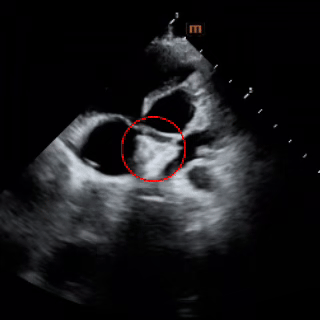

术中复测

左室长轴切面及四腔心切面复测缺损直径均约6mm

选伞考量:术中复测房间隔中部可见宽约6mm的回声失落,多普勒示左向右分流束;三尖瓣、二尖瓣少量反流;肺动脉轻度高压。综合考量选择BDASD-I 14封堵器,配14F鞘管施行介入封堵。